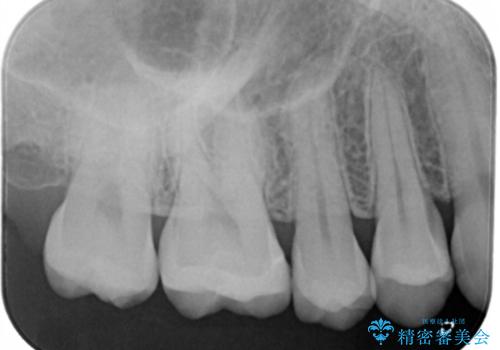

- 右上6番の保険材料で詰められた部分をセラミックにやり変え希望の患者様です。

切削量などを考慮し、セラミックインレーでの治療を選択しました。

う蝕が深くまで進行していたので、全て除去した上でCR裏層を行い形成、印象を行っています。